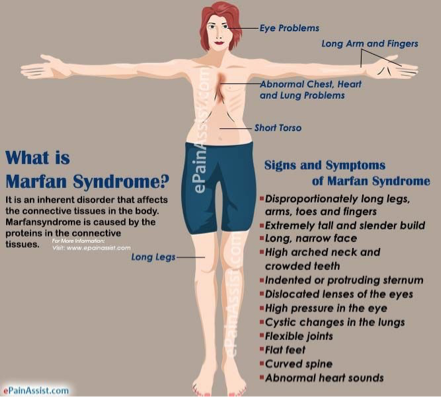

What does this refer to

Marfan’s syndrome

Risk factor of aortic aneurysm

Persons w/ Marfan syndrome are often males that are tall and “skinny”

Long extremities, fingers